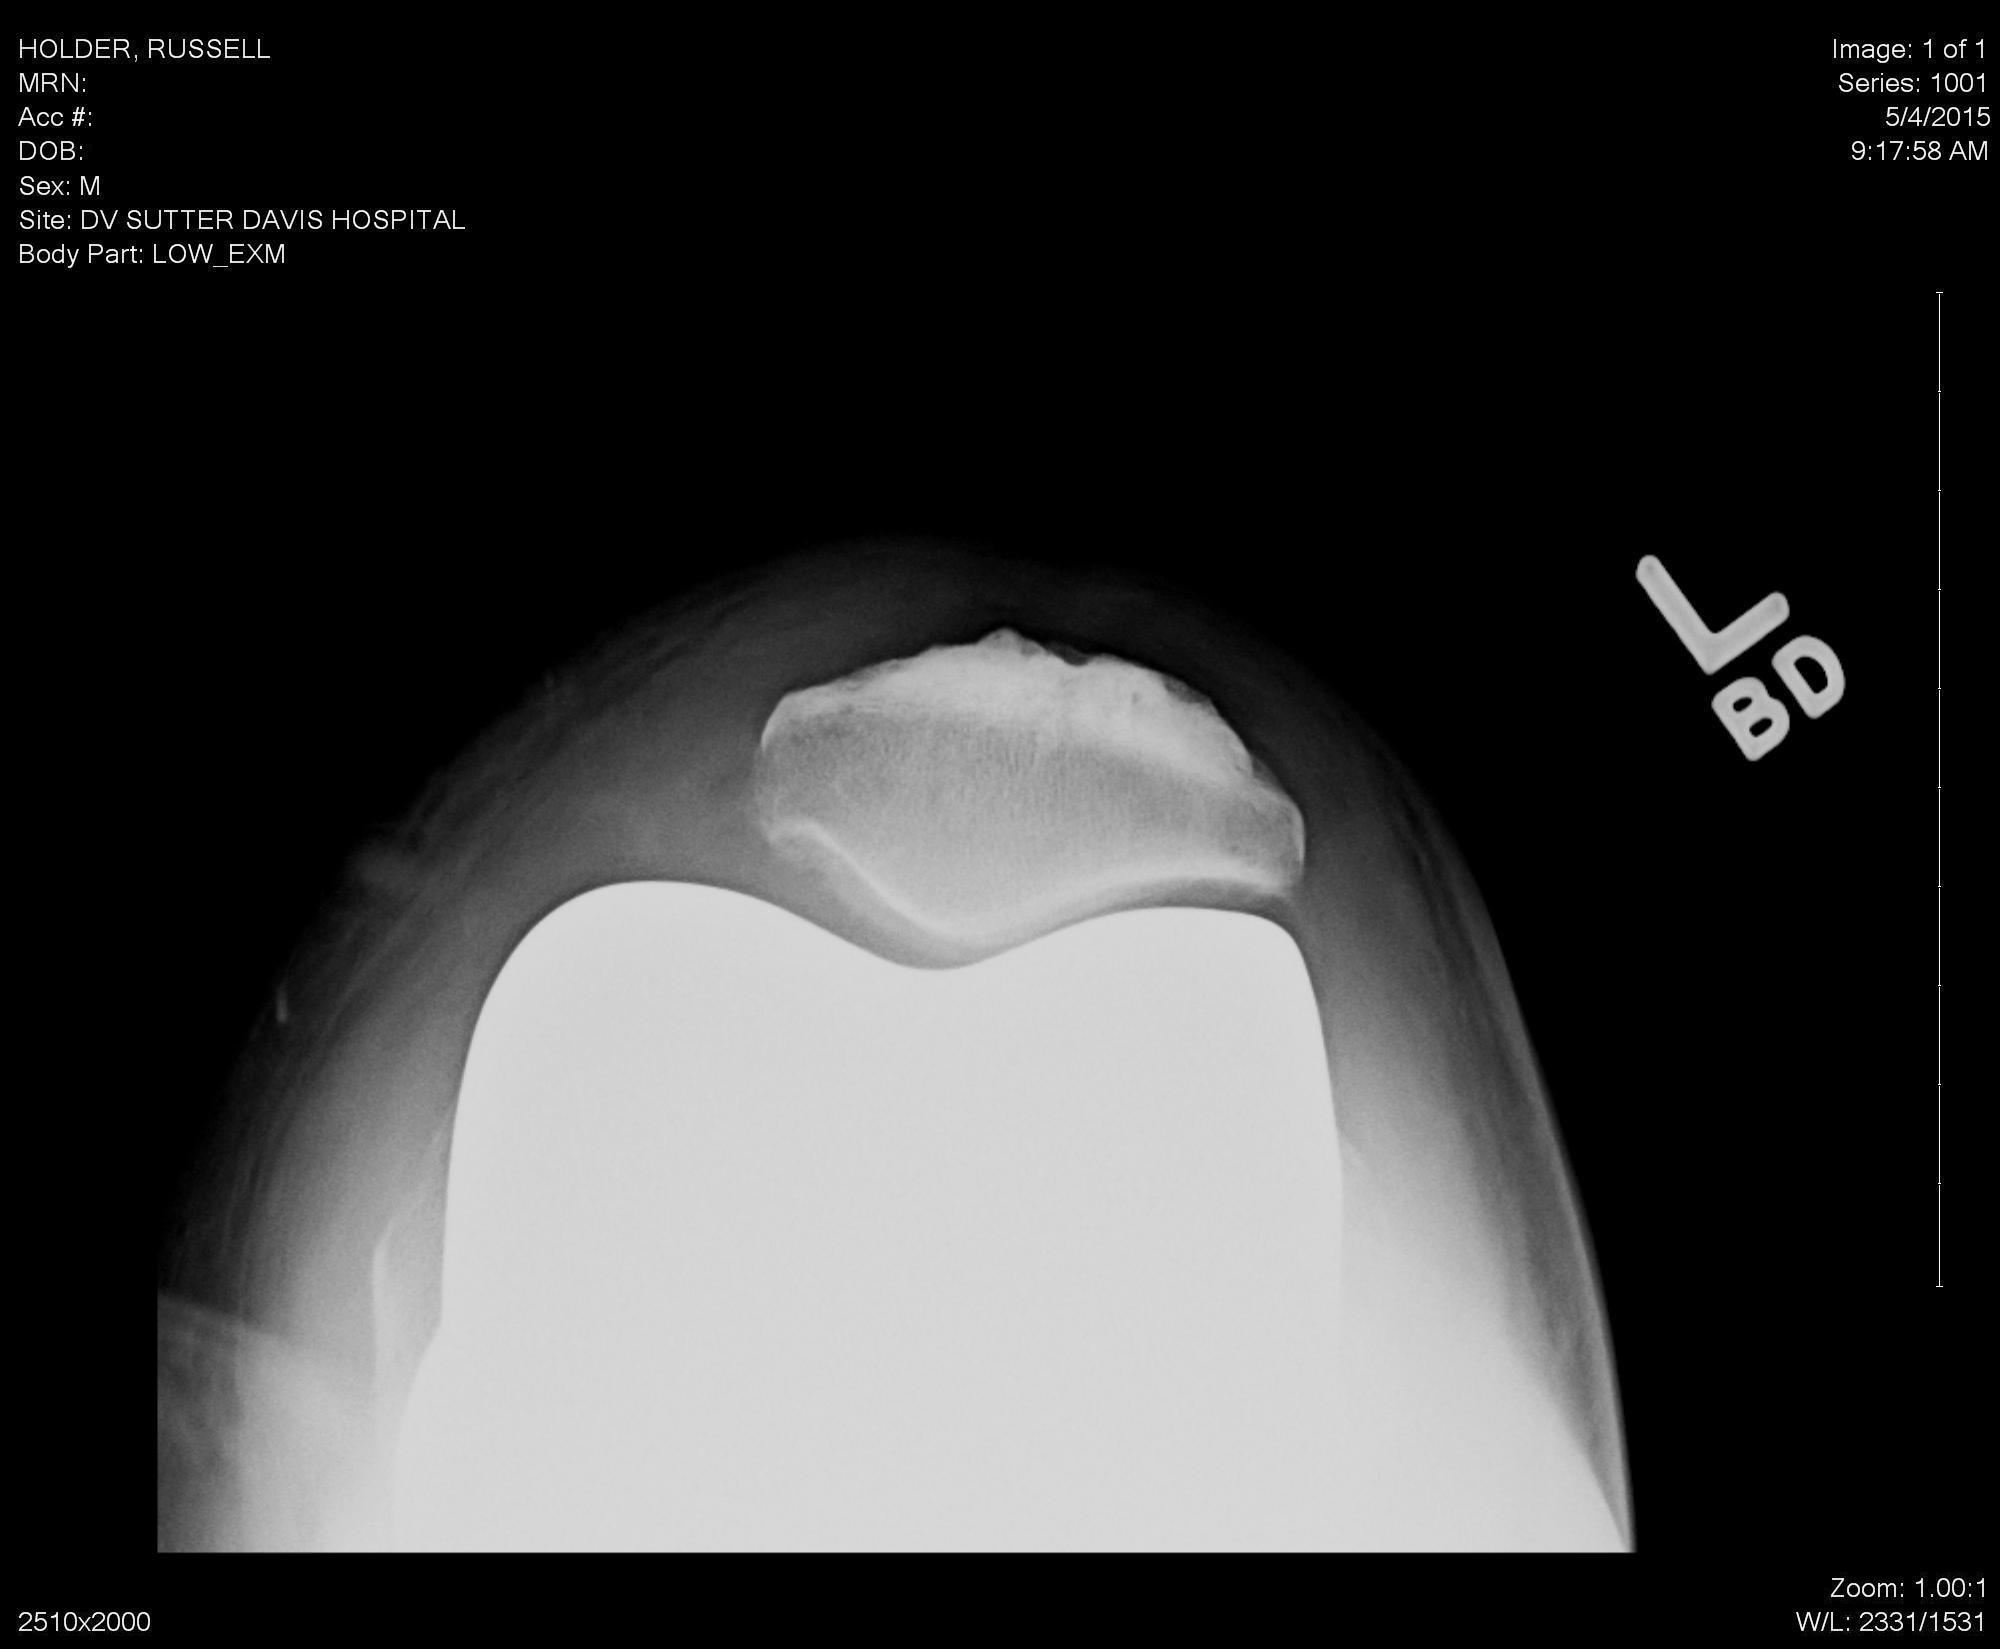

Right Sunrise X-ray, 10SEP14, 23MAY19 (click on X-ray to enlarge):

X-ray by Sutter Davis Hospital

X-ray by Kaiser Permanente Davis